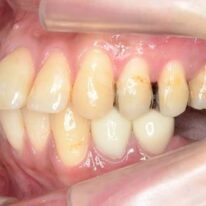

どうみても上顎が第一小臼歯を抜歯する必要があります。ところが抜歯して治療するほどの能力がこの矯正法にはありません。ブラケットとワイヤーで矯正治療するほどの能力はありません。そこで歯をディスキング(エナメル質の範囲内で削る)します。歯の幅を小さくする目的でおこないます。その結果、歯は長方形になってしまいます。また期待できるほどの隙間は得られません。

拡大し過ぎたのでしょうね。歯は外側に広がっています。しかし、骨は成長がないのでそれ以上増えません。歯が骨の外に出ていってしまいます。出っ歯になって大臼歯しか噛んでいない。口もとが突出して口ゴボになった可能性もあります。リテーナーをしっかり使用しないと後戻りします。